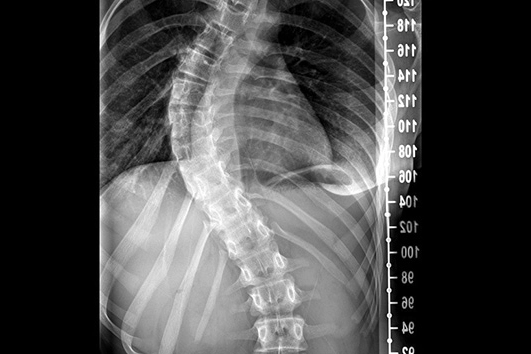

Skolyozun, özellikle büyüme çağındaki çocukları etkileyen ve omurganın anormal eğriliği ile karakterize edilen bir hastalık olduğunu söyleyen Omurga Cerrahı Op. Dr. Özgür Temiz, “Ergenlik döneminde fark edilmediğinde ilerleyebilen bu rahatsızlık, ciddi duruş bozukluklarına ve hareket kısıtlılıklarına yol açabilir” dedi.

Skolyoz konusunda aileleri uyararak erken teşhisin tedavi başarısını büyük ölçüde artırdığını vurgulayan Ortopedi ve Travmatoloji Uzmanı Op. Dr. Özgür Temiz, “Skolyoz, omuz seviyelerinde eşitsizlik, sırt ve belde asimetri, duruş bozukluğu ve bel ağrıları gibi belirtilerle kendini gösterebilir.

Eğer çocuklarda veya ergenlik çağındaki bireylerde bu belirtilerden biri ya da birkaçı fark edilirse, vakit kaybetmeden bir uzmana başvurulması gerekir” şeklinde konuştu.

Skolyoz tedavisinde, hastalığın şiddetine ve hastanın yaşına bağlı olarak farklı yöntemlerin uygulanabildiğini dile getiren OP. Dr. Temiz, hafif vakalarda düzenli takip ve fizyoterapinin yeterli olabileceğini ancak ilerleyen durumlarda korse tedavisi veya cerrahi müdahalenin gerekebileceğini belirtti.

“Özellikle 10-16 yaş aralığındaki çocuklarda ve kız çocuklarında daha sıklıkla görülen omurga eğriliğinin erken teşhis edilmesi, çocukların sağlıklı bir omurga yapısıyla yetişkinliğe adım atmasını sağlıyor. Aileler ve öğretmenler, çocuklarda duruş bozukluklarını fark ettiklerinde bir uzmana danışarak skolyozun erken teşhis edilmesine katkıda bulunabilirler. Omurga sağlığının korunması için düzenli doktor kontrolleri önemlidir ve erken müdahaleler ilerleyen yıllarda oluşabilecek kalıcı sağlık sorunlarını önleyebilir. Çocukların omurga sağlığını korumak için düzenli tarama ve kontrolleri ihmal edilmemelidir.”